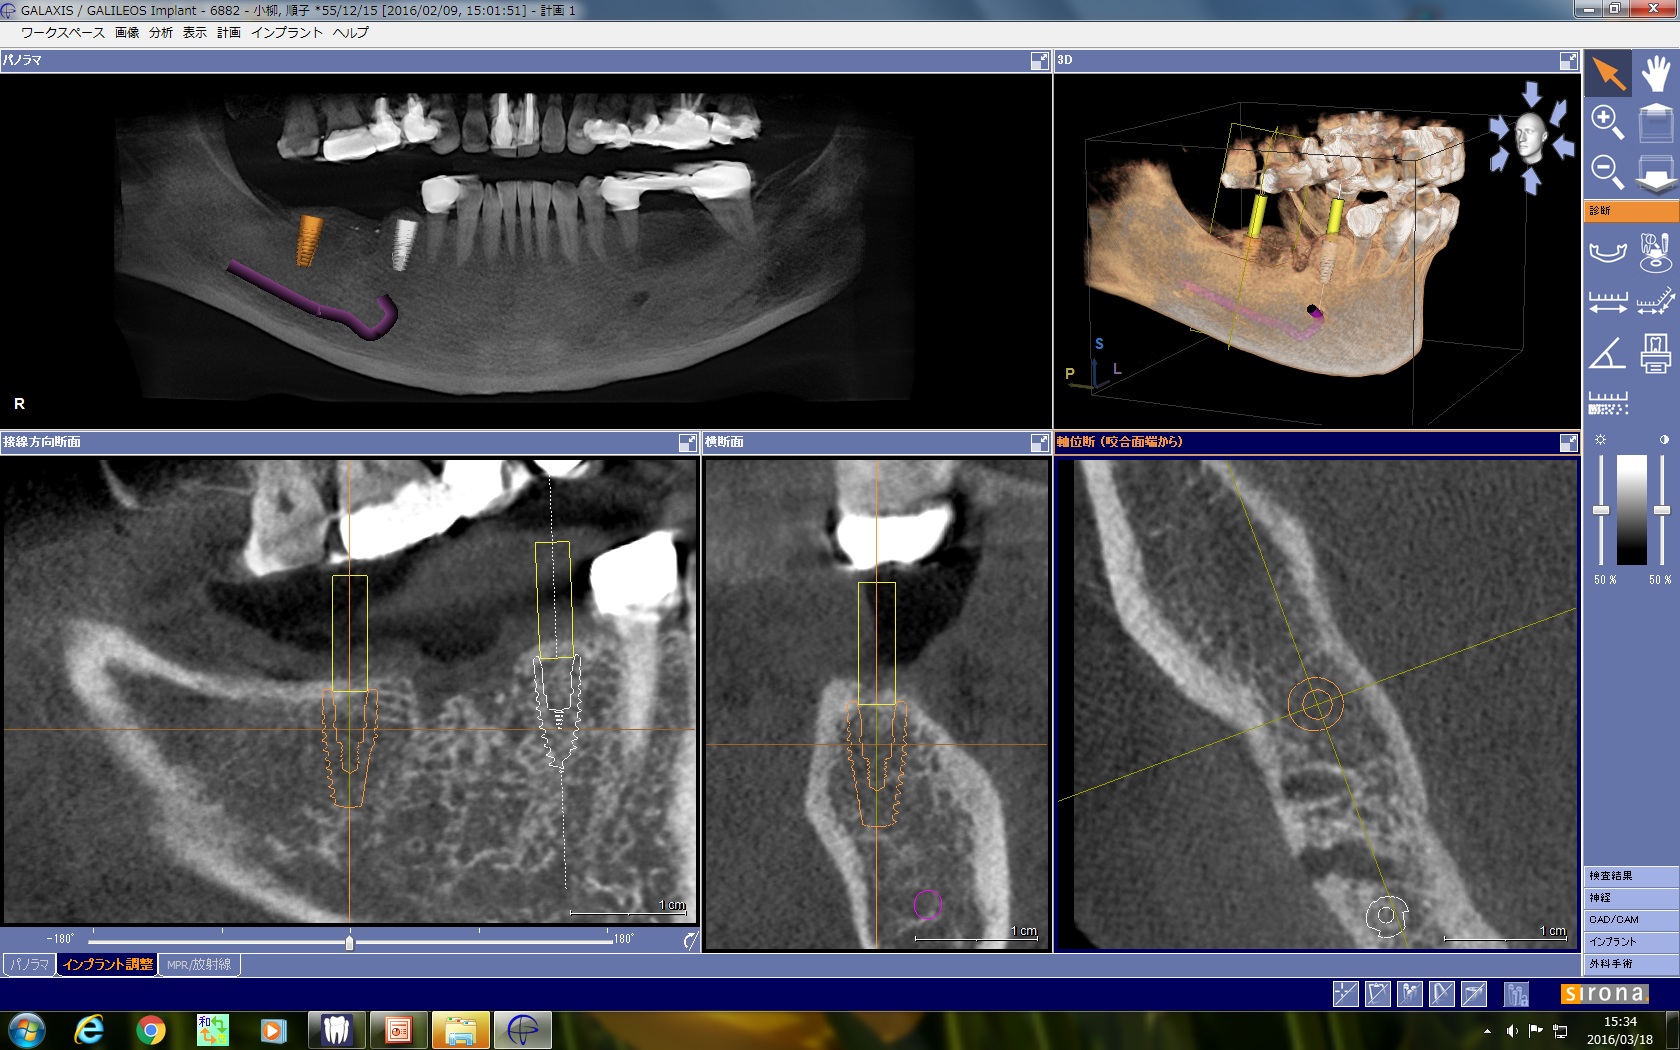

埋入部位の3D CTシミュレーション画像です。